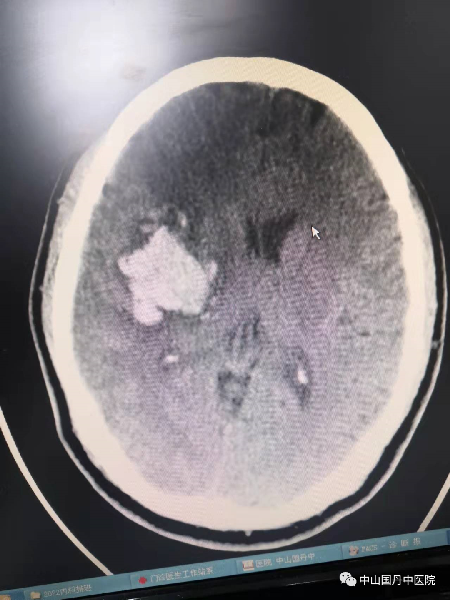

患者男性,55岁,因突发头痛、左侧偏瘫3小时余入院,入院时血压180/110毫米汞柱,神志模糊,左侧偏瘫,左上、下肢肌力0级,病情危急,医院启动急诊绿色通道,经脑CT扫描诊断为右侧大脑基底节区(内囊)出血并破入脑室,基底节区血肿量31.6毫升。

鉴于出血量超过30毫升,且位于重要功能部位。经院MDT多学科会诊,决定于发病6小时后实施颅内血肿微创穿刺碎吸引流术,由李明主任医师主刀,手术用一根3毫米直径针钻一体穿刺针经皮钻颅,再穿刺入深度达4.5厘米血肿中心,分次溶解、碎吸血肿。配合深静脉穿刺置管测中心静脉压、IUC镇痛、镇静等重症患者救治新技术支持治疗。

手术次日,患者神志转清醒,血压等调控在合理范围。术后第3天,血肿残余量仅10余毫升,顺利拨出引流针管。患者左下肢肌力逐渐恢复。于入院第8天出院,出院时左下肢肌力已至2~3级,能单独坐立。